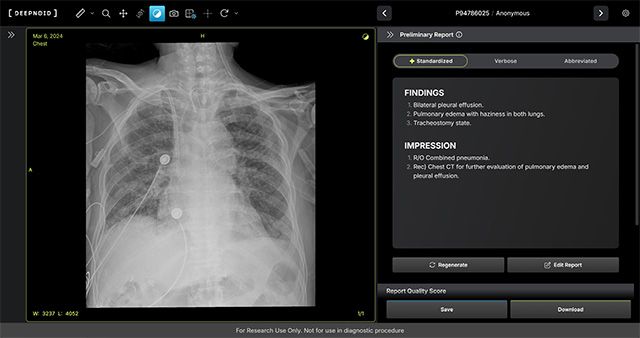

회사에 따르면 M4CXR은 흉부 X-ray 영상에서 41종의 병변을 분석해 수초 내 판독 소견서 초안을 자동 작성할 수 있는 것이 특징이다. 약 1,000만 건 이상의 판독 데이터를 기반으로 학습된 생성형 AI를 적용해, 영상의학과 전문의의 판독을 보조하고 응급 상황에서 신속한 예비 판독 결과를 의료진에게 제공할 수 있다는 설명이다.

휴먼영상의학센터 김성현 원장은 “흉부 X-ray는 임상 현장에서 가장 많이 시행되는 검사지만 판독 인력의 부족으로 속도에 한계가 있었다”며 “AI가 예비 판독 결과를 즉시 제공해 진단의 신속성을 높이고, 전문의의 판독을 보조해 정확성 향상에 기여할 수 있을 것으로 기대한다”고 말했다.